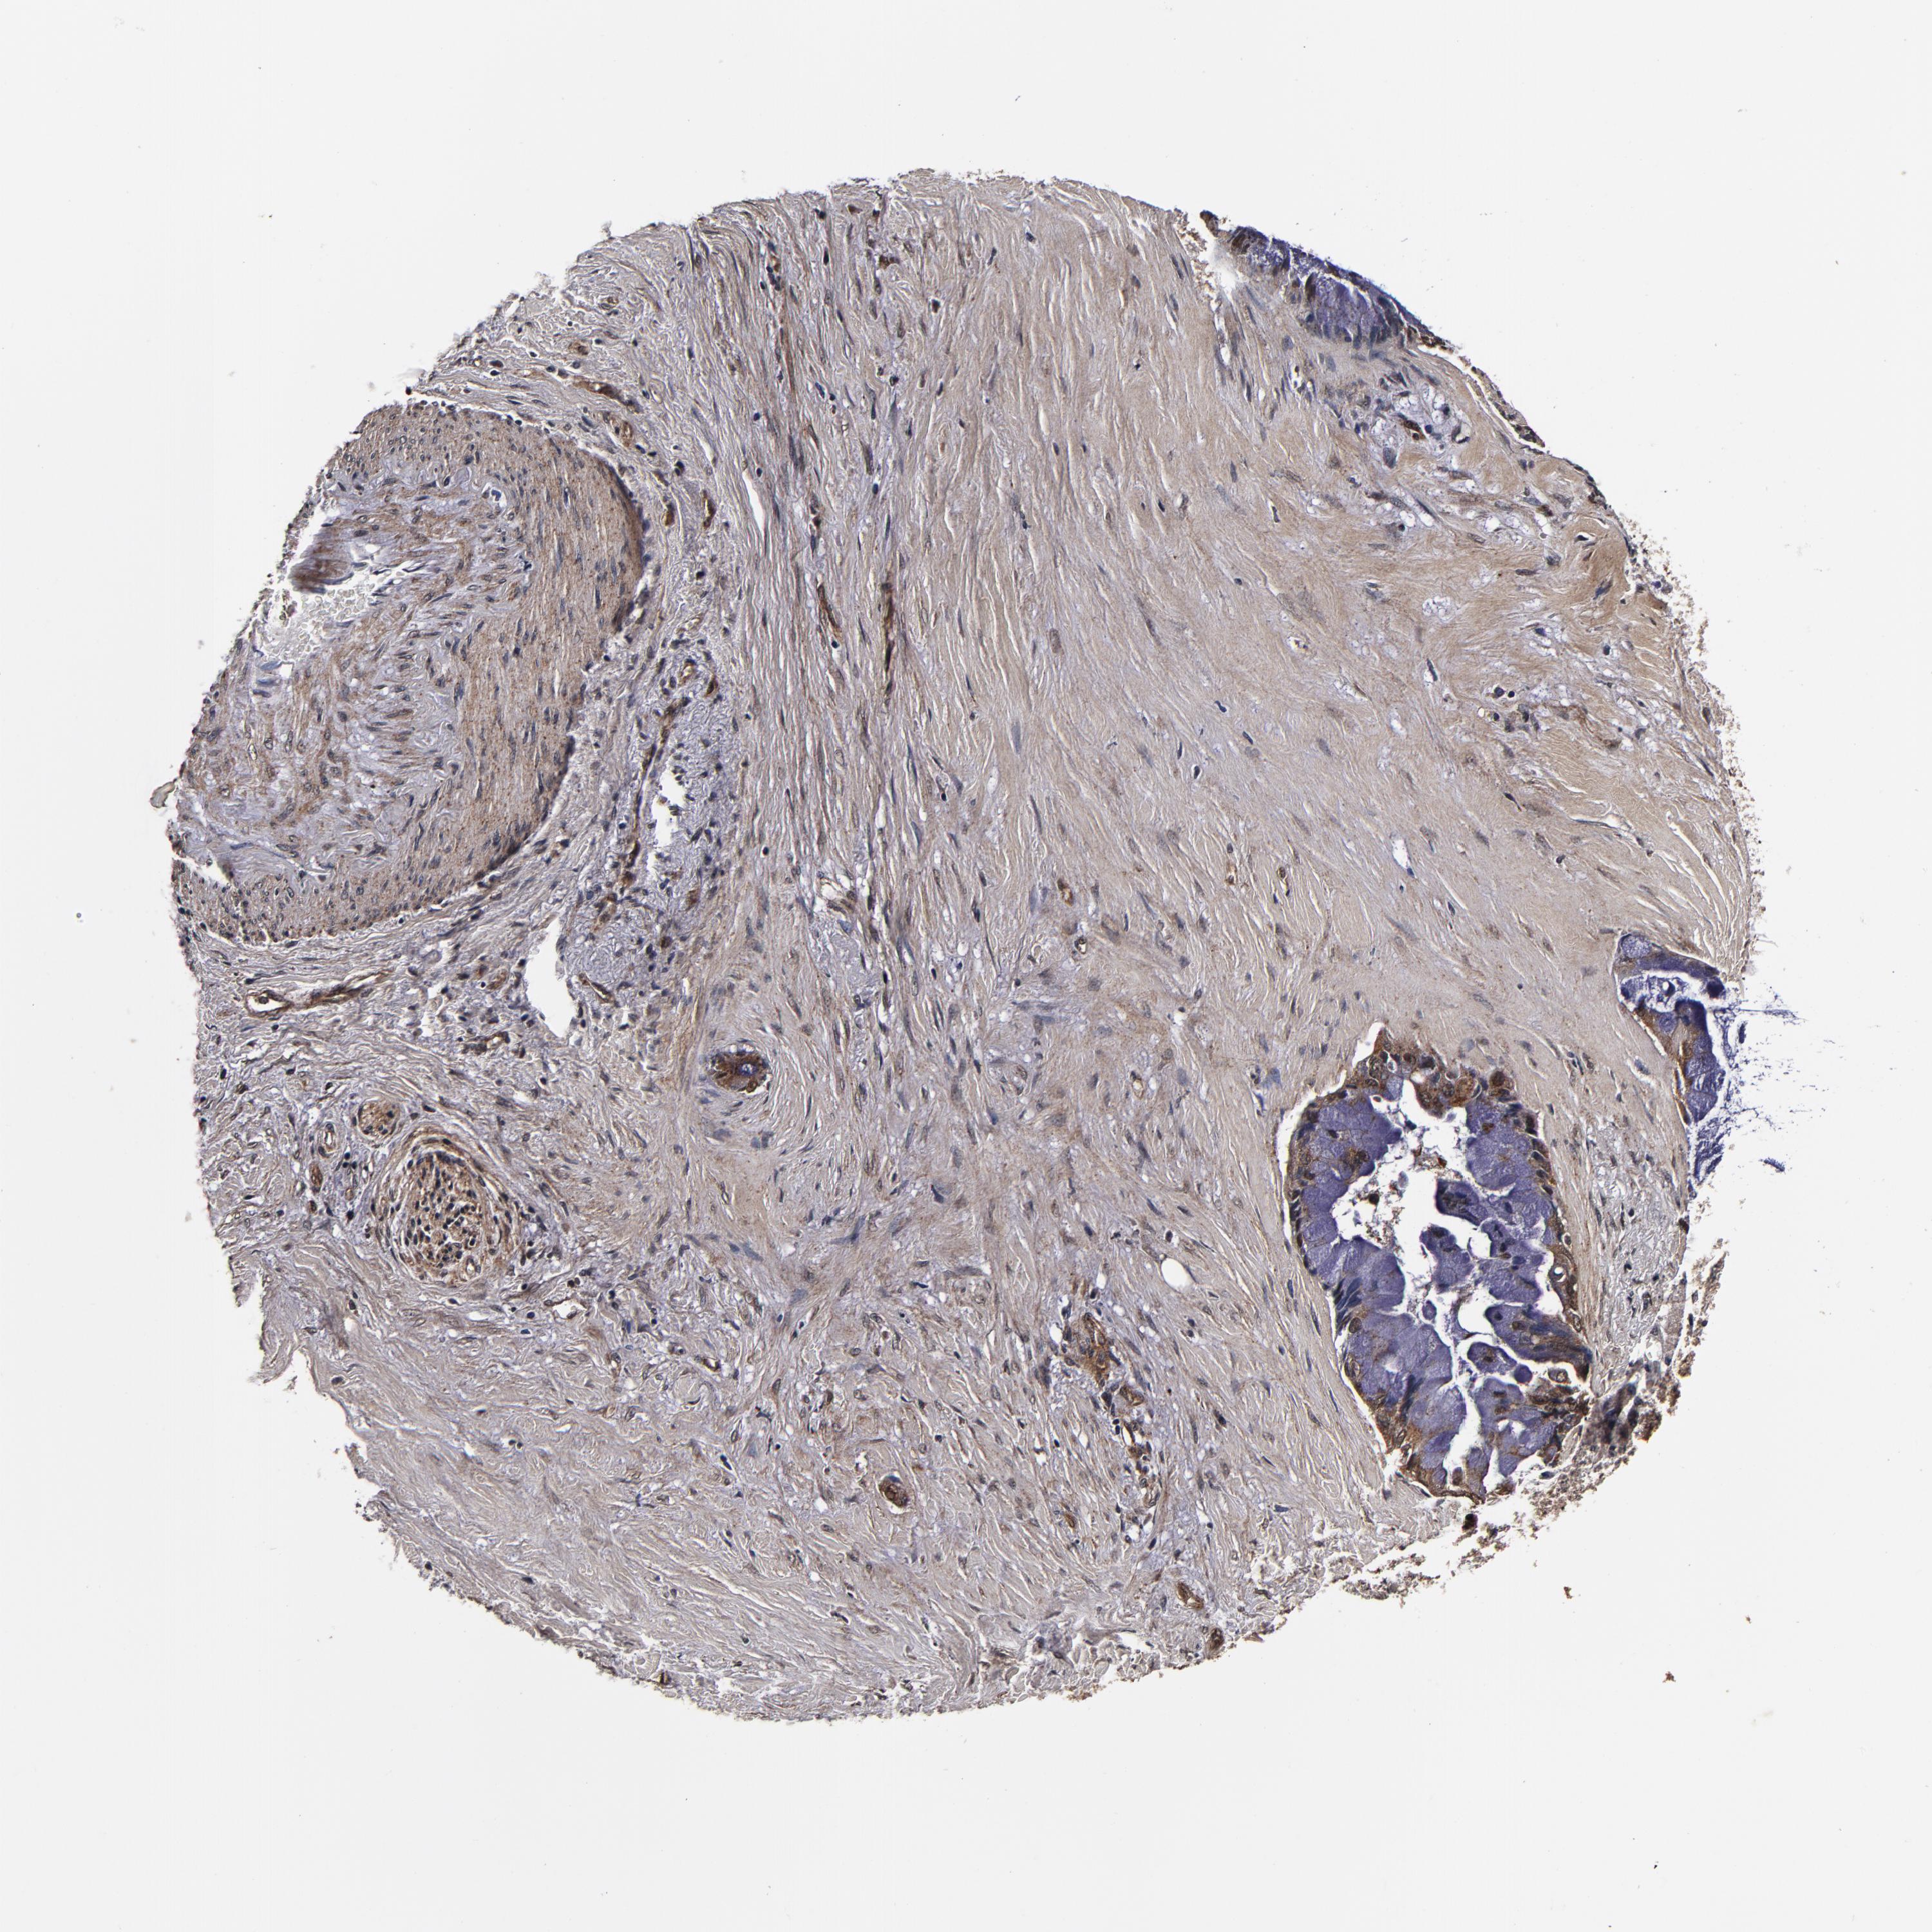

PANCREATIC CANCER - Protein expressioni

A mouse-over function shows sample information and annotation data. Click on an image to view it in a full screen mode. Samples can be filtered based on level of antibody staining by selecting one or several of the following categories: high, medium, low and not detected. The assay and annotation is described here.

Note that samples used for immunohistochemistry by the Human Protein Atlas do not correspond to samples in the TCGA dataset.

Antibody stainingi

Antibody staining in the annotated cell types in the current human tissue is reported as not detected, low, medium, or high, based on conventional immunohistochemistry profiling in selected tissues. This score is based on the combination of the staining intensity and fraction of stained cells.

Each image is clickable and will lead to virtual microscopy that enables deeper exploration of all samples and also displays staining intensity scores, fraction scores and subcellular localization as well as patient and tissue information for each sample.

Antibody HPA040390

Antibody CAB002611

Staining

High

Medium

Low

Not detected

Intensity

Strong

Moderate

Weak

Negative

Quantity

>75%

75%-25%

<25%

None

Location

Nuclear

Cytoplasmic/membranous

Cytoplasmic/membranous,nuclear

Adenocarcinoma, NOS